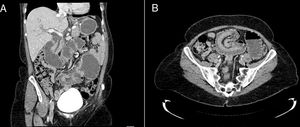

Analítica con colestasis y elevación de enzimas pancreáticas. Se realizó TC abdominal objetivando oclusión por invaginación yeyuno-yeyunal a nivel de pie de asa, dilatando de forma retrógrada el asa biliopancreática, vía biliar y remanente gástrico (fig. 1).